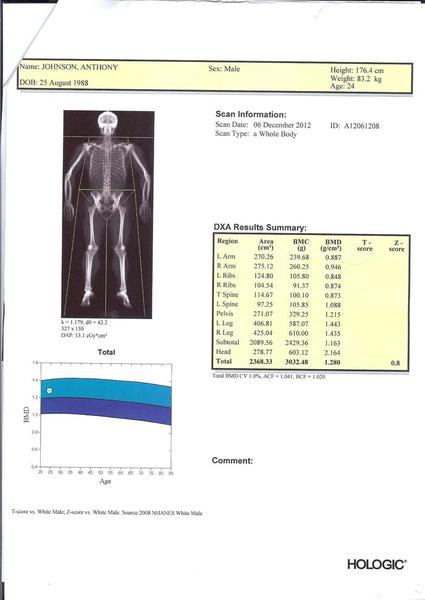

Image-4.jpg

Alright, I am confused because this man's pelvis area is only 271.07 cm2 while his head is 278.77. While it is clearly in the image that his pelvis is wider than his head but have comparable height. Can anyone explain this?